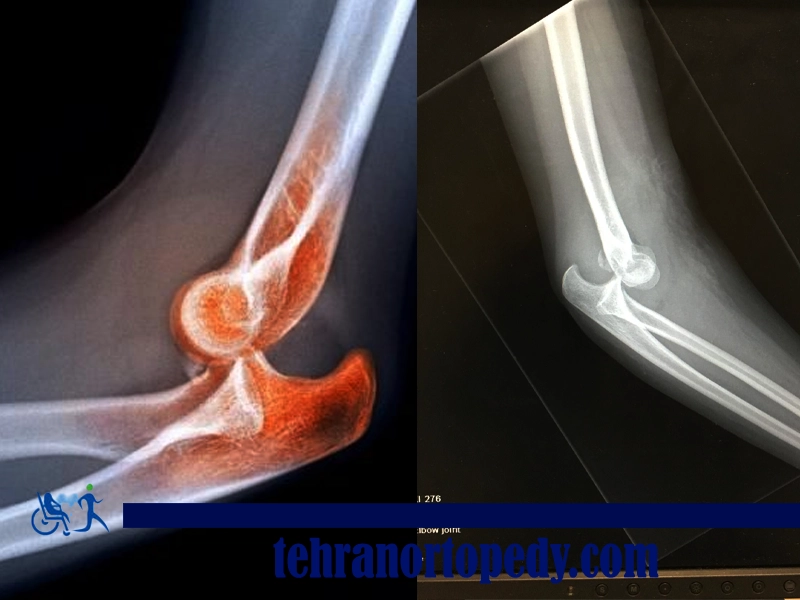

استخوان های اطراف آرنج پس از آسیب هایی مانند افتادن بر روی آرنج و دست یا ضربه مستقیم به آرنج، مانند تصادف رانندگی ممکن است دچار شکستگی شوند.

شایع ترین شکستگی های آرنج شکستگی های اوله کرانون و شکستگی های سر رادیوس هستند. علائم شکستگی آرنج، درد ناگهانی و شدید در آرنج همراه با تورم، بی حسی احتمالی و گزگز شدن دست و یا عدم توانایی برای صاف کردن بازو هستند.

دررفتگی آرنج رایج نیست و آرنج معمولاً هنگامی دچار دررفتگی می شود که فرد بر روی دست باز می افتد. وقتی دست با زمین تماس پیدا می کند، نیروی زمین خوردن به آرنج منتقل می شود که می تواند باعث پیچش یا چرخش آرنج از جای خود شود. به عبارت دیگر، ارتباط استخوان های آرنج -استخوان بازو و دو استخوان ساعد-از حالت طبیعی خود خارج می شوند.

دررفتگی علاوه بر اینکه با درد قابل توجه آرنج همراه است، اغلب باعث تغییر شکل زیاد آرنج، تورم و کبودی در اطراف مفصل می شود. برخی از افراد همچنین در دست خود احساس بی حسی و گزگز می کنند.

تشخیص درد آرنج عموماً به صورت بالینی، یعنی فقط با ارزیابی سابقه پزشکی شخص و معاینه انجام می شود. با این حال، گاهی اوقات، عکسبرداری از جمله رادیوگرافی برای رد تشخیص شکستگی مورد نیاز است.

برای تأیید یا پشتیبانی از تشخیص درد آرنج تان ممکن است نیاز به تصویربرداری های گوناگونی باشد. مثلاً برای تشخیص شکستگی یا دررفتگی آرنج باید رادیوگرافی انجام داده شود، در حالی که ممکن است برای بررسی بهتر تاندون عضله دوسر خصوصاً اگر در مورد پارگی تاندون تردیدی وجود داشته باشد، ام آر آی توصیه شود.